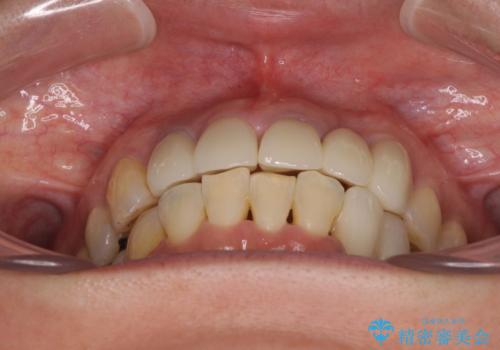

矯正治療によって前歯にスペースを作り、左右対称となるようにオールセラミッククラウンにて補綴治療を行うとしました。

他にも奥歯の咬み合わせに問題があったので、全顎的な矯正治療を行い、前歯以外にも口を開けたときに目立つ奥の銀歯をセラミッククラウンにて補綴治療を行うこととしました。

前歯の横幅が大きいことも気になっていたので、矯正治療で前歯5本の幅をコントロールしながら移動させ、治療開始前より一回りサイズの小さいセラミッククラウンを装着することができました。